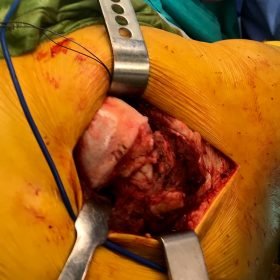

Σε αυτό το σημείο η Αρθροπλαστική Ισχίου αποτελεί μονόδρομο.

Παραδοσιακά οι αρθροπλαστικές ισχίου αποτελούνται από μια μεταλλική μπάλα – σφαίρα τοποθετημένη σε μια πλαστική κοιλότητα (κοτυλιαία πρόθεση).

Η πλαστική επιφάνεια στήριξης φθείρεται με την πάροδο του χρόνο, με ρυθμό μάλλον σχετιζόμενο με το επίπεδο δραστηριότητας του ατόμου. Αυτό έχει σαν επακόλουθο νεότεροι ασθενείς με μεγαλύτερο προσδόκιμο ζωής να έχουν αυξημένο ρίσκο αναγκαιότητας δεύτερης αρθροπλαστικής ισχίου (αναθεώρησης – Revision) επέμβαση που είναι πολυπλοκότερη και υπόκεινται σε υψηλότερο κίνδυνο επιπλοκών. Βάση των ανωτέρω, ιστορικά, η αρθροπλαστική ισχίου σπανίως εφαρμοζόταν σε ασθενείς κάτω των 60 ετών.

Χάρη στα νέα τεχνολογικά επιτεύγματα έχουν παραχθεί επιφάνειες στήριξης που ανταποκρίνονται σε μεγαλύτερα επίπεδα δραστηριότητας και αναμένεται να έχουν μεγαλύτερη διάρκεια ζωής. Αυτές οι καινούριες επιφάνειες στήριξης είναι συνήθως μέταλλο πάνω σε ειδικό σκληρότερο πλαστικό ή κεραμικό πάνω σε κεραμικό. Ως εκ τούτου, είναι τώρα πολύ πιο σύνηθες, νεότεροι ασθενείς να χειρουργούνται καθώς η πλειονότητα αυτών, που η αρθρίτιδα τους προκαλεί αφόρητους πόνους, επιλέγουν να έχουν ποιότητα ζωής από το να ζουν με τον πόνο.

Η αρθροπλαστική ισχίου αποτελεί μια αποτελεσματική επέμβαση αποκατάστασης και πρέπει να εφαρμόζεται μόνο όταν οι ασθενείς δεν είναι σε θέση να αντέξουν άλλο τον πόνο και την ανικανότητα και εφόσον τα πλεονεκτήματα καθώς και οι πιθανοί κίνδυνοι της μεθόδου έχουν εξηγηθεί πλήρως από το χειρουργό και έχουν κατανοηθεί από τον ασθενή.